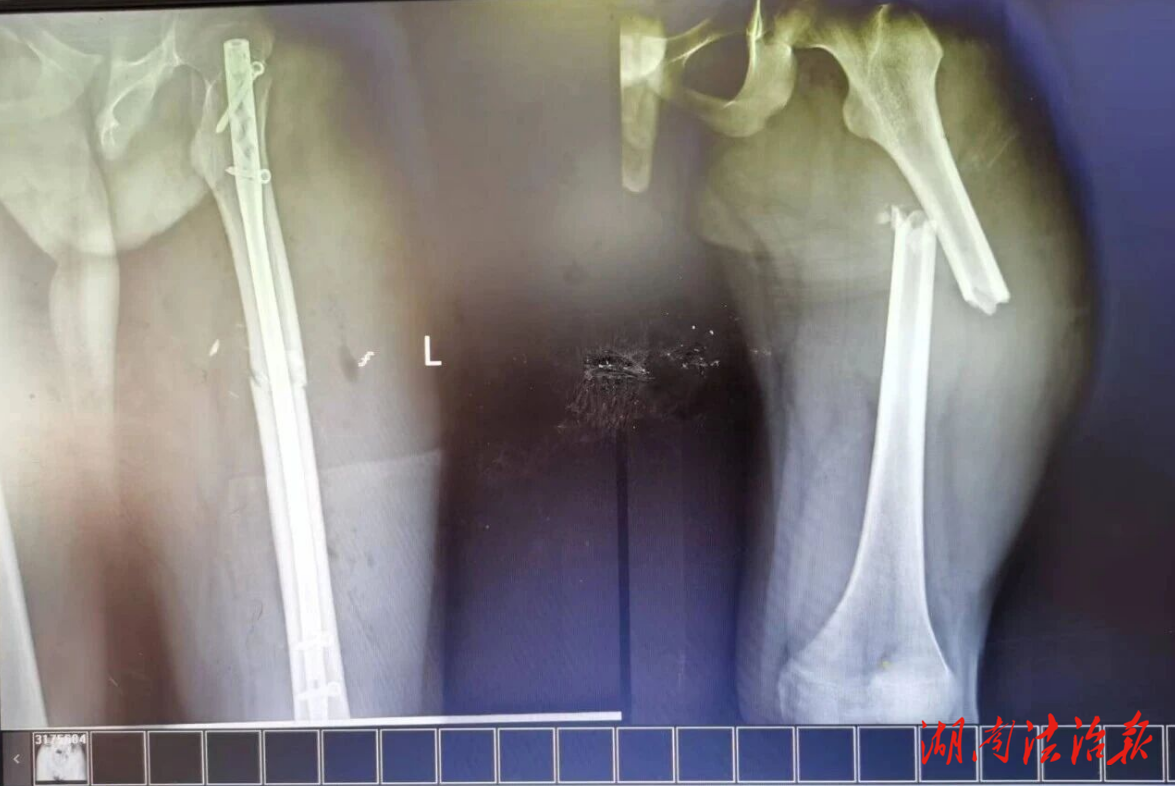

手術(shù)中,團(tuán)隊(duì)默契配合、精細(xì)操作,順利將髓內(nèi)釘置入患者骨髓腔,為骨折端搭建堅(jiān)固支撐,實(shí)現(xiàn)完美復(fù)位。術(shù)后復(fù)查顯示骨折對(duì)位對(duì)線良好,內(nèi)固定位置精準(zhǔn)。得益于微創(chuàng)手術(shù)優(yōu)勢(shì),患者術(shù)后疼痛輕微、恢復(fù)迅速,在醫(yī)護(hù)指導(dǎo)下早期開(kāi)展功能鍛煉,現(xiàn)已順利拆線康復(fù)出院。